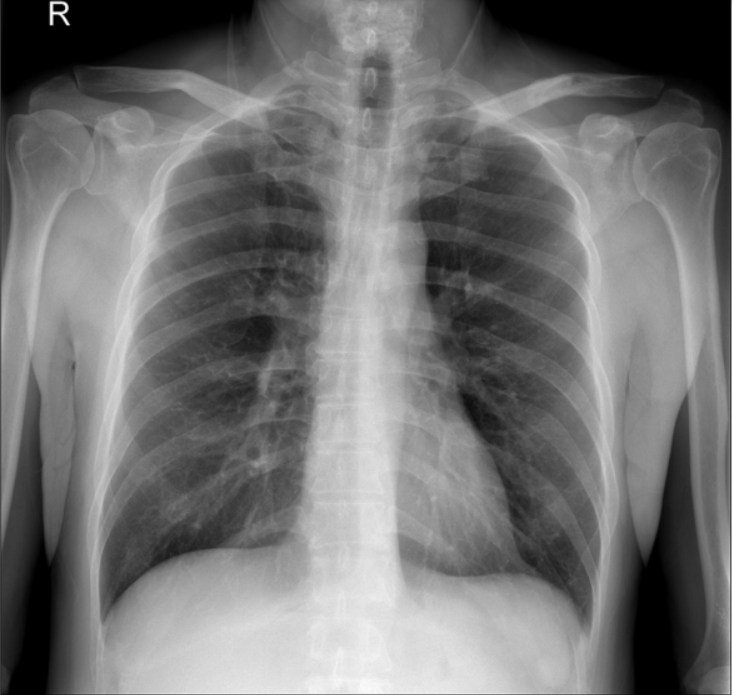

植入物取出后,胸片显示锁骨骨折完全愈合,随访1年,肩锁关节脱位保持良好复位